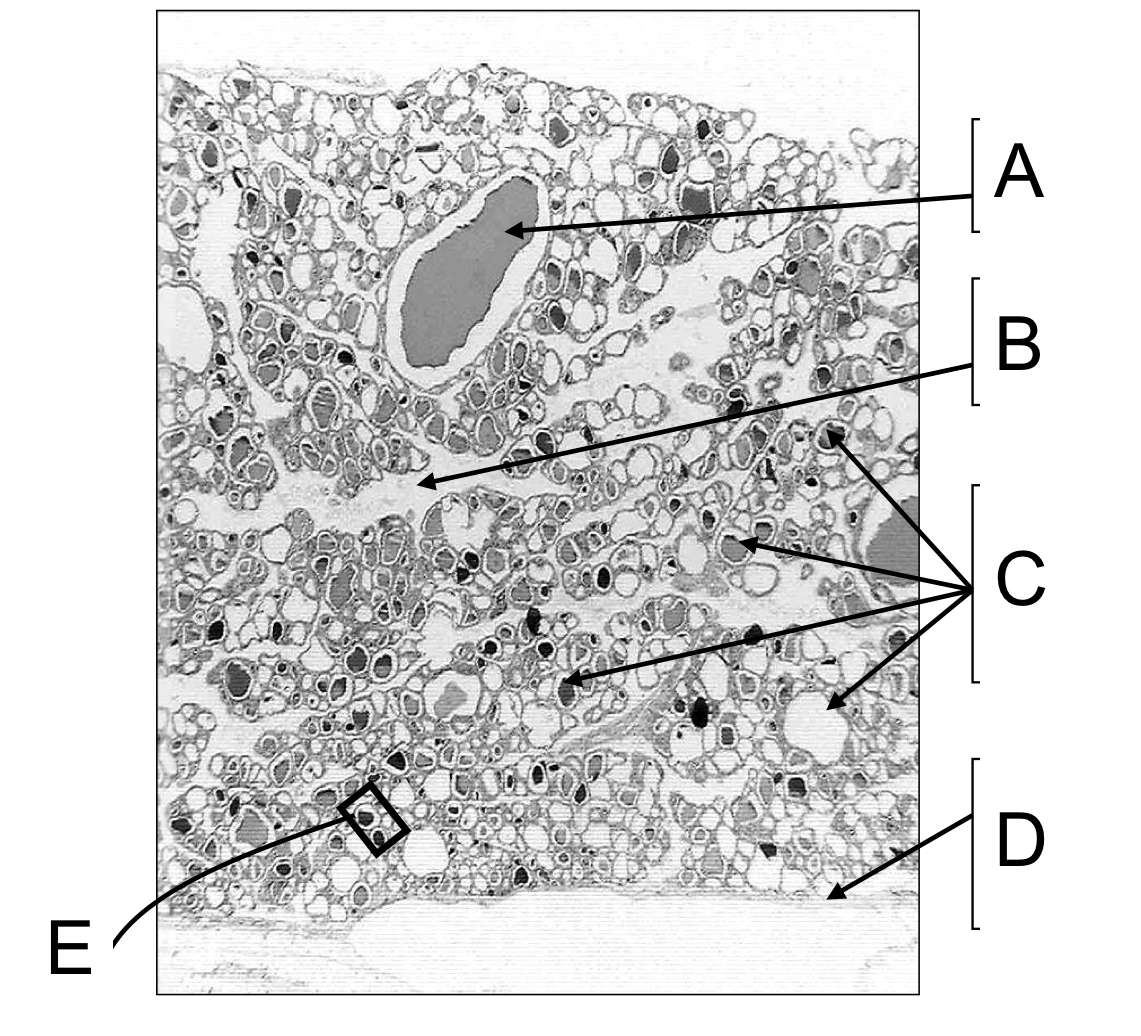

A - Unusually large thyroid follicle containing shrunken colloid

B - Shrinkages of thyroid lobules during tissue processing causes artefactual spaces at the septa

C - The tyroid is composed of numerous follicles. The colloid in some have fallen out during tissue processing

D & E- A fibrous capsule envelops the thyroid gland. Septa derived from the capsule subdivides the gland into lobules

A - Simple cuboidal epithelia

B - Thyroid colloid - a glycoprotein complex of thyroglbulin which incorporates thyroid hormones prior to their release